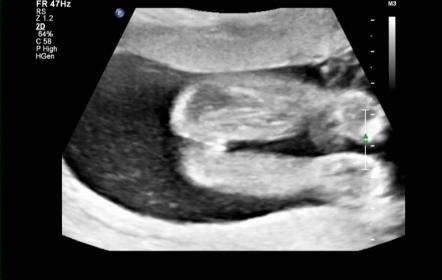

Hello lovely ladies :) Soooooo had my 20 week anatomy scan this morning and as you all guessed it right bubs is a :ballerina: We're over the moon that she is healthy!! The tech took a nub shot to confirm gender though which I thought was a little odd as Im so used to seeing potty shots so Ive snapped a few off my dvd and included her nub shot but just hoping to get your confirmation too please xx